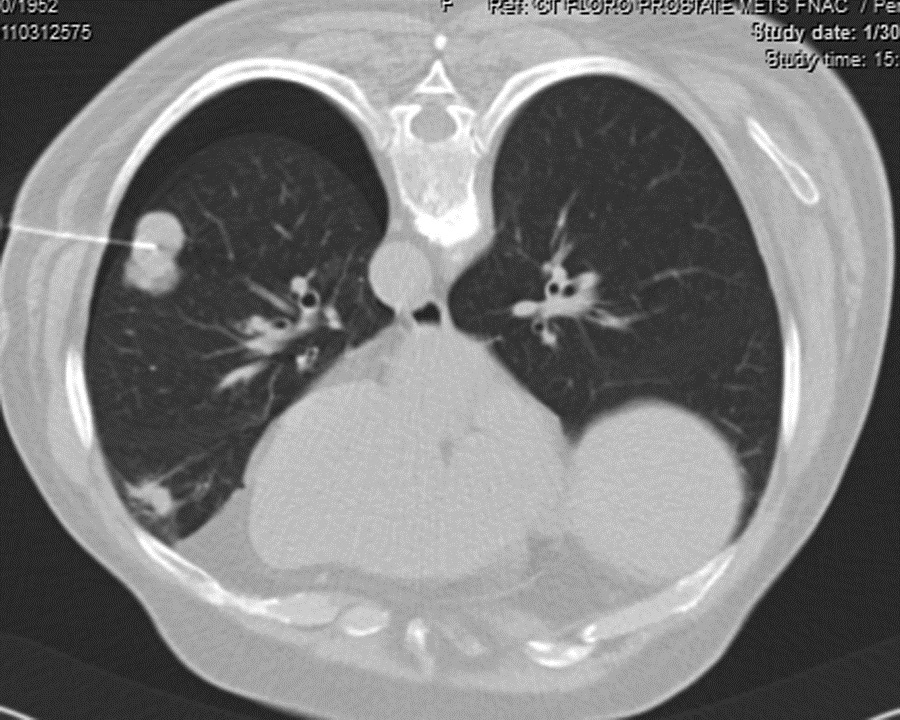

Prostate cancer usually metastasizes to regional lymph nodes and bone followed by distant organs. Here, we present a case of elderly man who had isolated respiratory symptoms and finally turned out to be metastasis from prostate cancer. Rarity of isolated pulmonary metastases of prostate cancer without bone and lymph node involment prompted us to report this case which was diagnosed by CT guided FNAC.